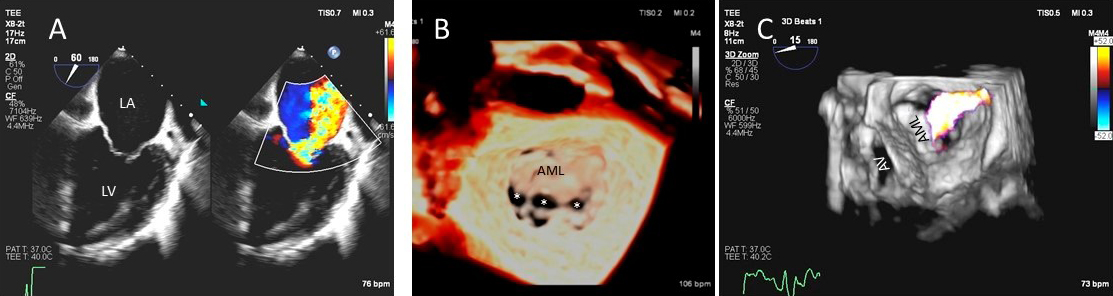

As opposed to degenerative MR, mitral valve leaflets in secondary MR may be normal but MR results from leaflet mal-coaptation due to a dilated mitral annulus as in dilated cardiomyopathy or due to tenting of mitral leaflets due to LV infarct remodeling causing outward displacement of papillary muscles and tethering of chordae attached to these papillary muscles. Mal-coaptation may be along the entire mitral leaflet coaptation plane mostly in functional MR (Fig. 3A–C) or localized to some scallops commonly seen at the P3 scallop of the mitral valve in the presence of a remodeled infero-posterior myocardial infarction causing tethering of the chordae to P3 scallop (ischemic MR).

Fig. 3.Functional Mitral regurgitation. (A) Transesophageal echocardiogram biplane view shows a dilated LV with mitral valve coaptation point displaced into the LV and central MR jet. (B) 3D TEE showing central mitral leaflet malcoaptation (white asterisks). (C) 3D TEE surgical view of the mitral valve showing severe central mitral regurgitation. LA, left atrium; LV, left ventricle; AML, anterior mitral.